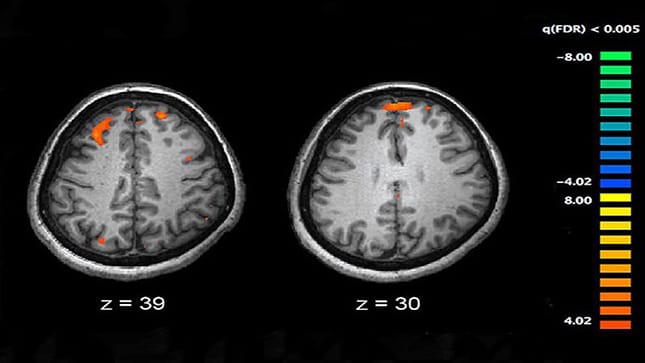

Os resultados do perfil metabólico de rotina do paciente, hemograma, hormônio estimulante da tireoide, provas de função hepática, perfil lipídico, exame de urina, toxicológico de urina, e níveis séricos de drogas e álcool foram normais. Foi feita uma ressonância nuclear magnética do crânio, cujo resultado foi normal (Figura 1).

Figura 1.